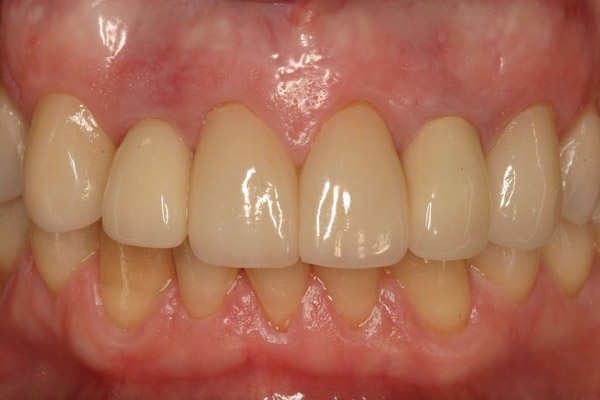

Figure 19  The post-implantation and post-restoration view shows esthetically pleasing, symmetric crowns and mucosal contours, with the Nos. 7 and 10 implant prostheses blending in imperceptibly with the natural dentition. Restoration courtesy of Dr. Jeffrey Warren.

Figure 19